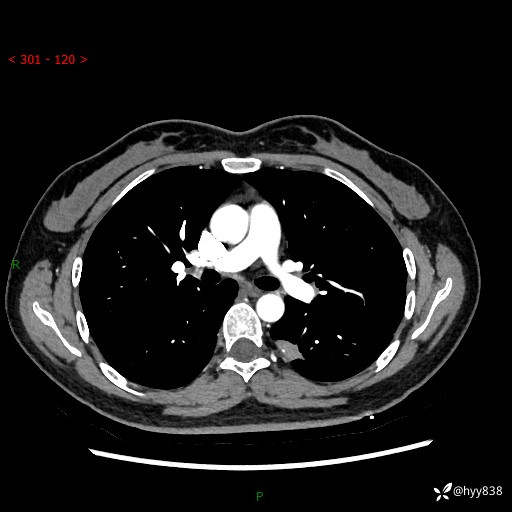

【患者信息】:36岁/女

【主诉】:左侧下胸部阵发性疼痛2周,乏力1周

【现病史及既往史】:患者自诉2周前饮酒后出现左侧下胸部阵发性疼痛,不随呼吸改变,无咳嗽咳痰、头晕头痛、咳血、呼吸困难等不适,于当地第一人民医院查胸部CT提示肺部感染,随后前往我院门诊给予抗感染(左氧氟沙星)治疗1周,自诉胸痛较前好转,感乏力、头晕,偶尔干咳,无咳痰,无发热、畏寒、胸闷、咯血、四肢酸痛、腹泻、腹痛等不适,门诊复查胸部CT提示:左肺下叶感染,病灶较前增加增大,遂以“肺部感染”收入我科。 起病以来,患者精神、饮食、睡眠可,大小便正常,体力体重无明显变化。

【检查】:胸部CT增强(外院平扫)